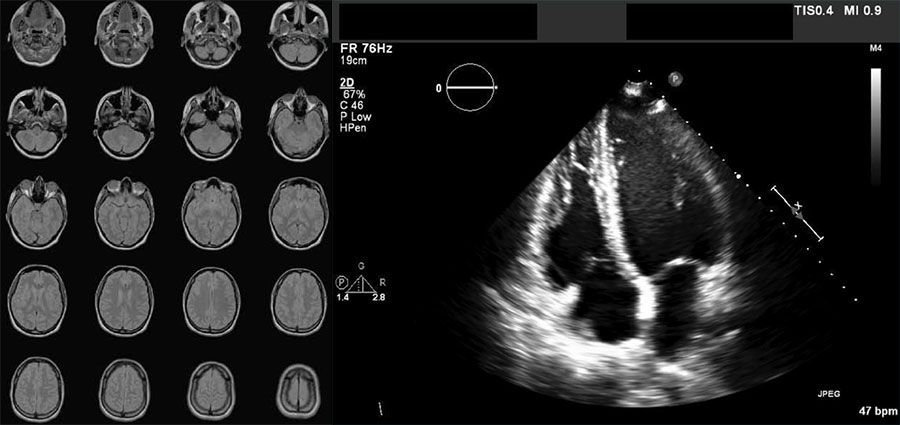

Ejemplos de imágenes en formato DICOM: serie de 20 imágenes de una IRM de un cerebro y una imagen de ecocardiografía.

Serie de imágenes de RM de un cerebro (izquierda) y una ecocardiográfica (derecha) almacenadas en formato DICOM.